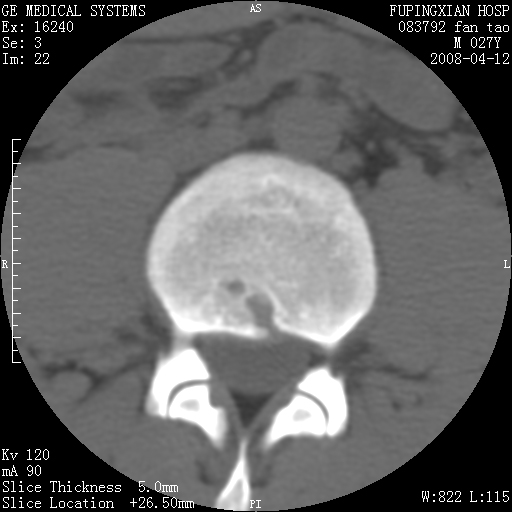

以下是引用前行在2008-4-13 13:53:00的发言:[br]椎间盘髓核终板下突出形成许莫氏结节及椎间盘突出,建议mr检查

以下是引用xclzq_910在2008-4-13 12:43:00的发言:[br]这个应该没什么了,椎间盘突出后反应性骨质吸收硬化.建议mr